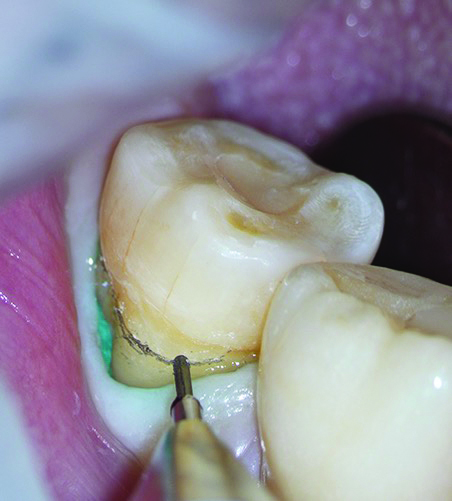

The final step of the clinical workflow involves complete isolation of the operative site using a rubber dam under the DOM to prevent contamination before cementation. After isolation was achieved the restoration was tried in to verify full seating, thus ensuring a precise marginal fit and tight proximal contacts, with smooth transitions and no overhangs (Figure 16).

Once the restoration fit was confirmed, the cementation process commenced by etching the tooth abutment with phosphoric acid while simultaneously protecting the adjacent tooth using Teflon tape (Figure 17). This was followed by rinsing and drying the abutment in accordance with the adhesive protocol (Figure 18).

Fig 16. Initial intraoral fit check, from all aspects, was done under the microscope, directly and indirectly.

Figure 16

Fig 17. Acid etching of the tooth abutment.

Figure 17